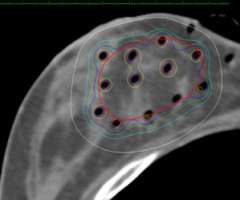

Examples show how the radiation dose (the colored lines, with the white lines representing 50% of the dose) is targeted to the area where the original tumor was using three different partial breast radiation techniques (SAVI, Contura, Tube and Button).

An axial CT scan showing the distribution of the hollow tubes (black dots) and the distribution of the targeted radiation. The white line represents a line encompassing 50% of the radiation dose. One can see how much of the skin and chest wall are spared